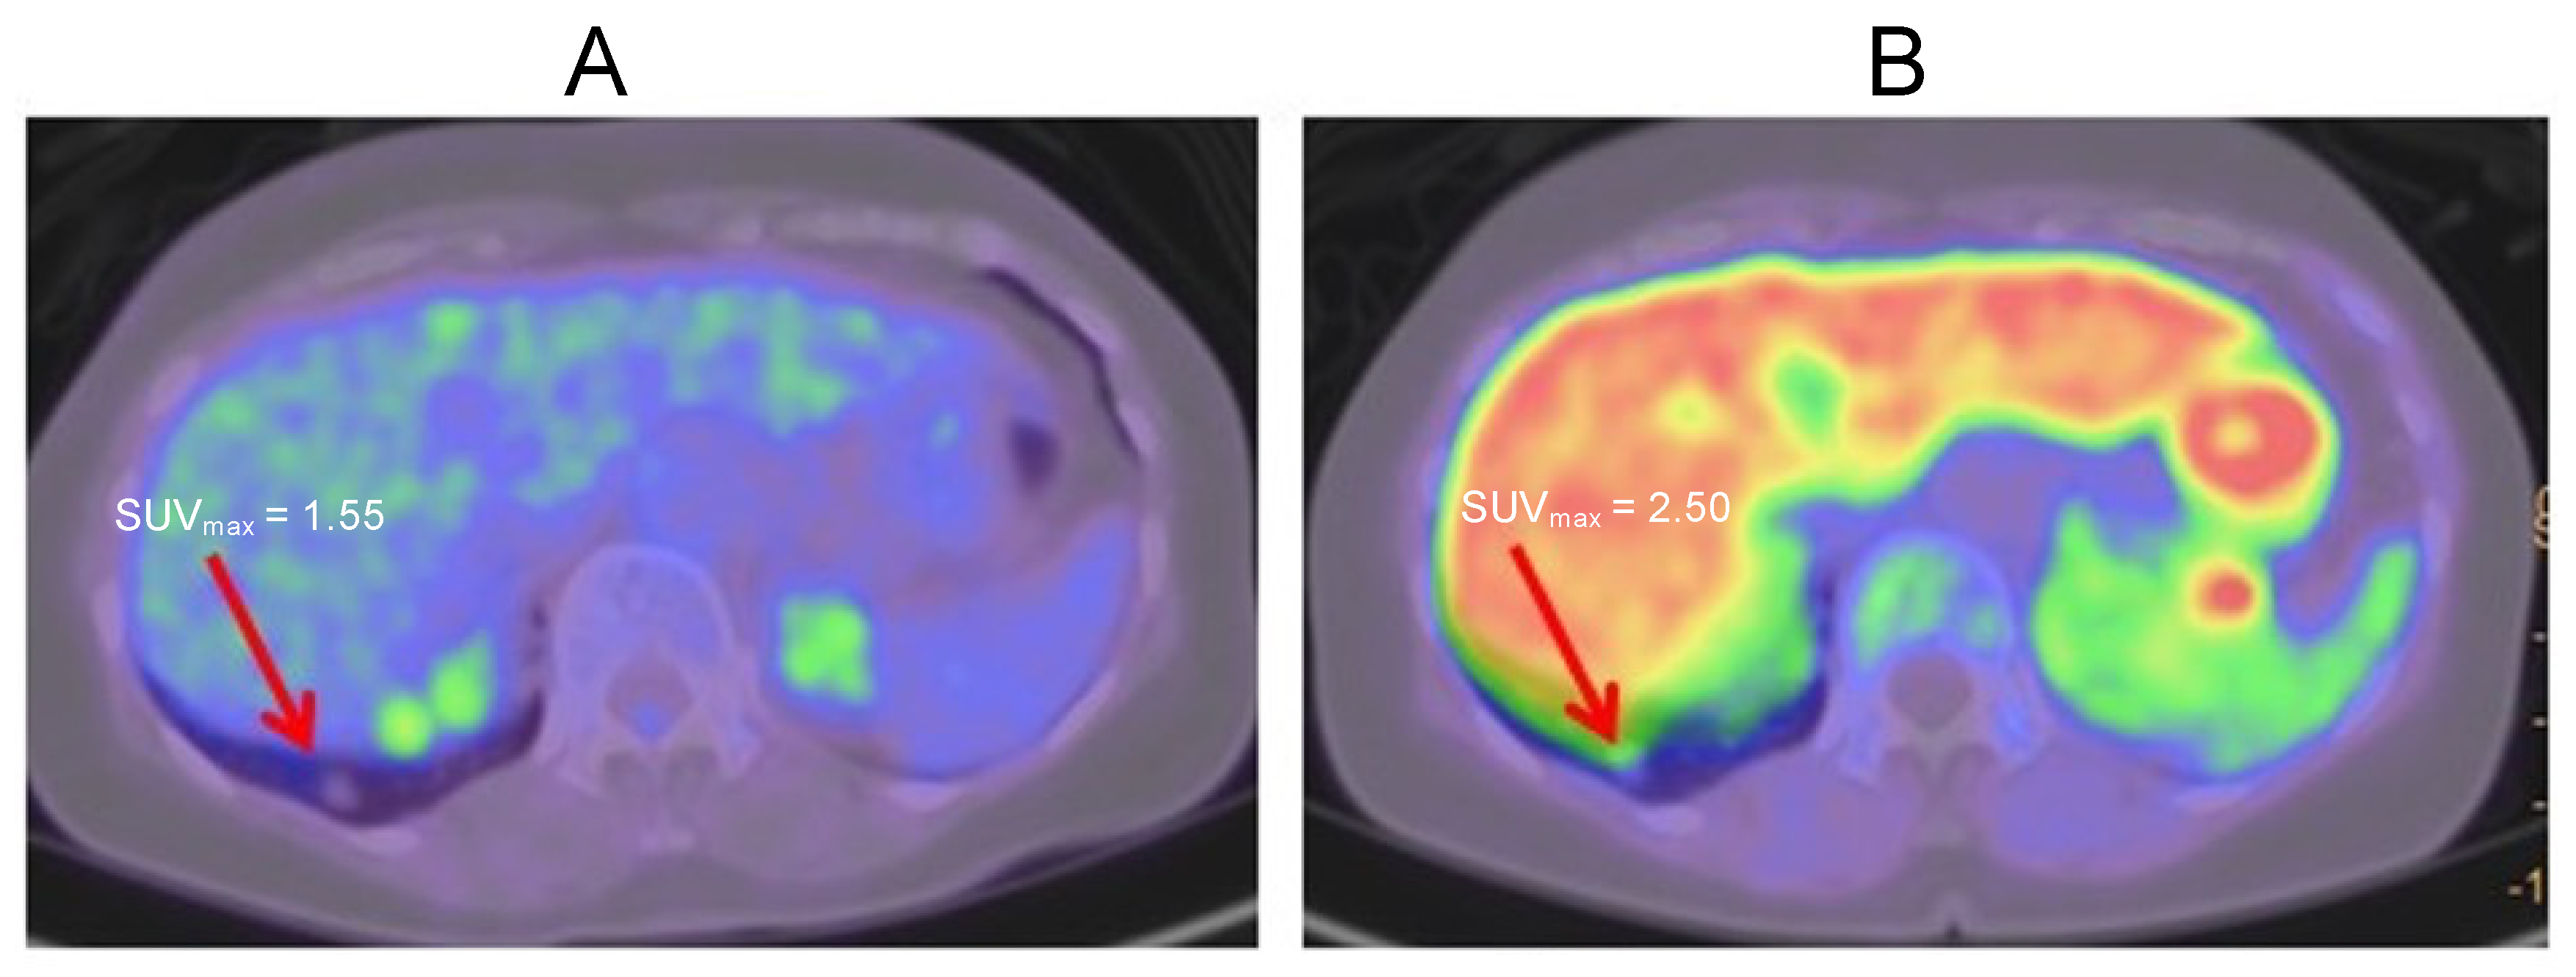

2.3. Case 3

2.4. Case 4